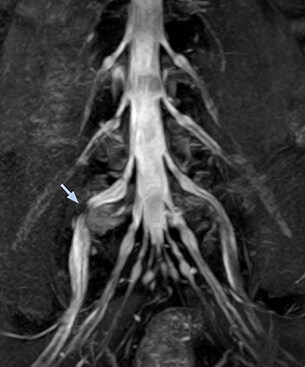

“In such case, we would then browse through axial T2-weighted MR images slice by slice and mentally reconstruct the actual situation based on both radiculography and MRI. Fortunately, NerveVIEW can now very well show nerve courses and presence of nerve compression or edema in one single image series.”   “We have often seen NerveVIEW directly depict details of the nerve compression that were not observed by radiculography. Therefore, we think that with NerveVIEW we can reduce the number of invasive examinations, especially for some patients with lumbar plexus symptoms.”

“Before NerveVIEW, diagnosis by MRI alone was sometimes difficult, unless there was a strong suspicion based on clinical symptoms,” says Shoji Yabuki, MD, DMSc, Orthopedic surgeon at Fukushima Medical University School of Medicine. “This is why we routinely perform selective lumbosacral radiculography (nerve root block) and x-ray in such cases. However, radiculography can only depict nerves as far as the contrast agent reaches. When a nerve is distorted by compression, the contrast agent will not pass through this compressed area, preventing us from evaluating the full nerve compression.”

The key concept in MR neurography, Dr. Yabuki stresses, is the ability to directly visualize spinal nerves, versus inferring the presence of pathology indirectly. “Before NerveVIEW, we estimated compression of the nerve by looking for the presence or absence of fat signal on other MR images,” he says.

“For example, in sagittal images, when the presence of fat is observed in the intervertebral foramen, it suggests that there is a margin around the nerve. Similarly, the absence of fat indicates that the nerve is being compressed. So, we used to deduce nerve compression indirectly. With NerveVIEW, however, we can observe the condition of the nerves directly, regardless of the presence or absence of fat. We always prefer such direct observation of anatomy over having to make an inference about it.”

“Although symptoms of typical disc herniation and atypical hernia are very similar, the actual site of herniation is different. It is therefore important to characterize the nerve’s condition both inside and outside of the intervertebral foramina.   “Conversely, if we see no abnormality in NerveVIEW, we can assume at least that there is no severe condition that requires surgery. Like this, it can help us avoid unnecessary surgery. NerveVIEW can have a tremendous impact in this way.”

“NerveVIEW is really useful for those cases where a nerve disorder is strongly suspected based on the clinical examination but our regular MRI images do not show any findings. These atypical herniations and spinal canal stenosis, occurring in 5% to 15% of the total lumbar herniation/stenosis cases are our main target when using NerveVIEW,” says Dr. Yabuki.